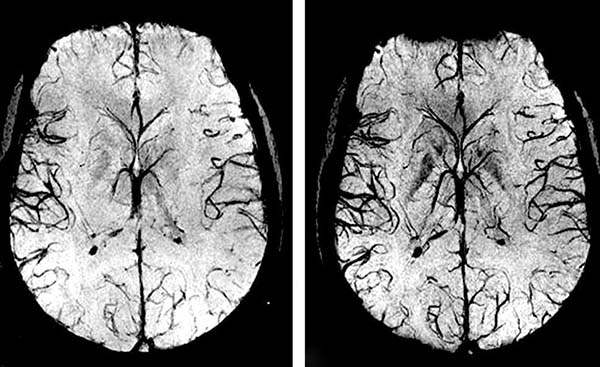

Smadzenes un insults

Aizsargājiet smadzenes — novērsiet insultu!

Hipertensija ir galvenais insulta riska faktors Latvijā. Katru gadu vairāk nekā 5 000 latvieši pārdzīvo insultu — un lielākā daļa varēja to novērst.

• Augsts spiediens bojā smadzeņu kapilārus un palielina asiņošanas risku

• Hroniska hipertensija pasliktina atmiņu un kognitīvās funkcijas

• Tonerin uzlabo asinsriti smadzenēs un mazina mikrotrombu risku

• Regulāra lietošana aizsargā smadzeņu šūnas no oksidatīvā stresa

• Klientu aptaujā 87% atzīmēja uzlabotu koncentrēšanos pēc 4 nedēļām